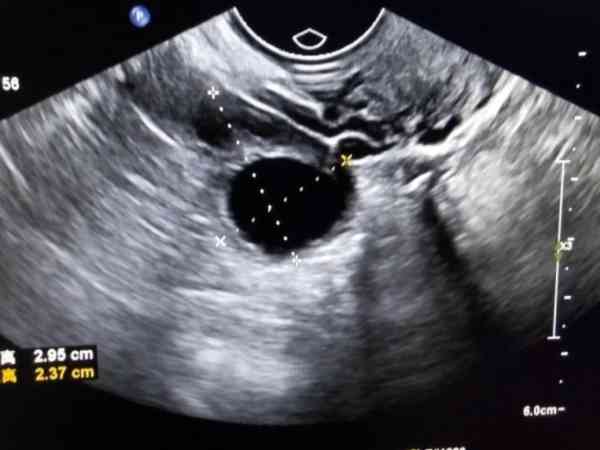

監測卵泡報告想要看卵泡多大了,可以觀察報告單上的數字,比如說報告單上提示18*18mm,就說明有一個卵泡已經長到18mm了,此時卵泡已經發育成熟,有排卵的可能性,回去後安排同房即可。

通過報告單上的數字就能瞭解到卵泡發育情況,有的也會在數字後面對卵泡發育情況做一個解讀,如果不知道卵泡發育多大,可以詢問醫生,在檢查後醫生也會分析結果,有不懂得也可以問。